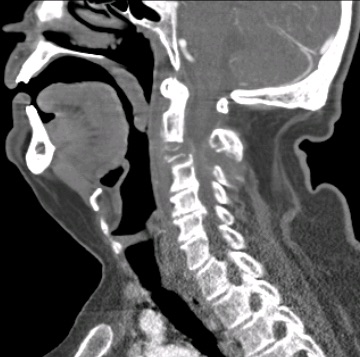

Paciente de 71 años que presenta enfermedad oncológica en estadio paliativo por tumor renal de años de evolución. Presentó fractura patológica C3 con clínica de tetraparesia súbita e incapacidad para mantener bipedestación (ASIA C). En comité de Neuroncología se acordó tratamiento quirúrgico paliativo.

Se realizó una descompresión posterior del arco de C3 asociando una artrodesis occipitocervical. La afectación del pedículo/pars de C2 por el tumor recomendaba obviar esa vértebra en la reconstrucción.

Obsérvese afectación pedículo/pars C2 por el tumor